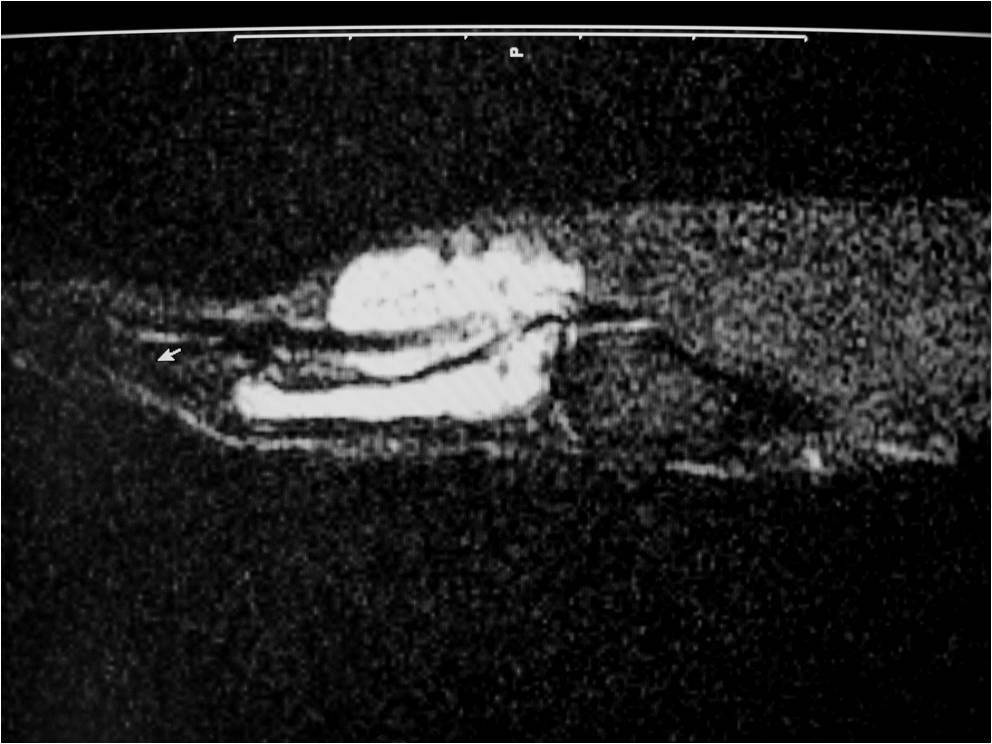

MRI

• Isointense to muscle T1

• Low to intermediate T2

• May bloom on gradient echo (hemosiderin deposition)

• May demonstrate intense enhancement

Fig. 2-5: MR images of the hand with a giant cell tumor of tendon sheath shows a mass isointense to muscle on T1W and intermediate to high signal on T2W images. The lesion does not infiltrate the bone.